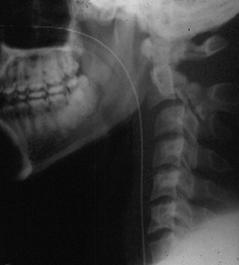

TRAUMA CERVICALA

Incidenta laterala Incidenta

laterala Incidenta

Aspect normal Imagine

normal